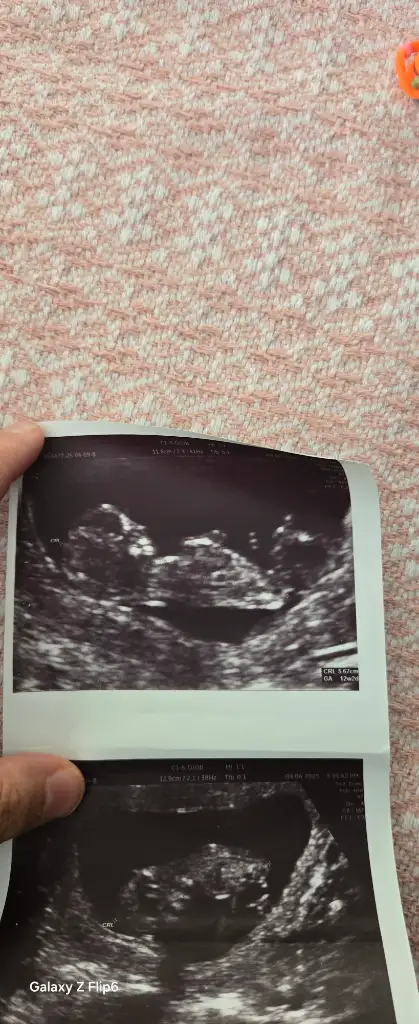

13 haftalik bakarmisiniz nedir sizce

Eklentiler

• IMG_5072.webp

IMG_5072.webp

40 KB · Görüntüleme: 156

• IMG_5071.webp

IMG_5071.webp

20,1 KB · Görüntüleme: 102

• IMG_5070.webp

IMG_5070.webp

27,2 KB · Görüntüleme: 108